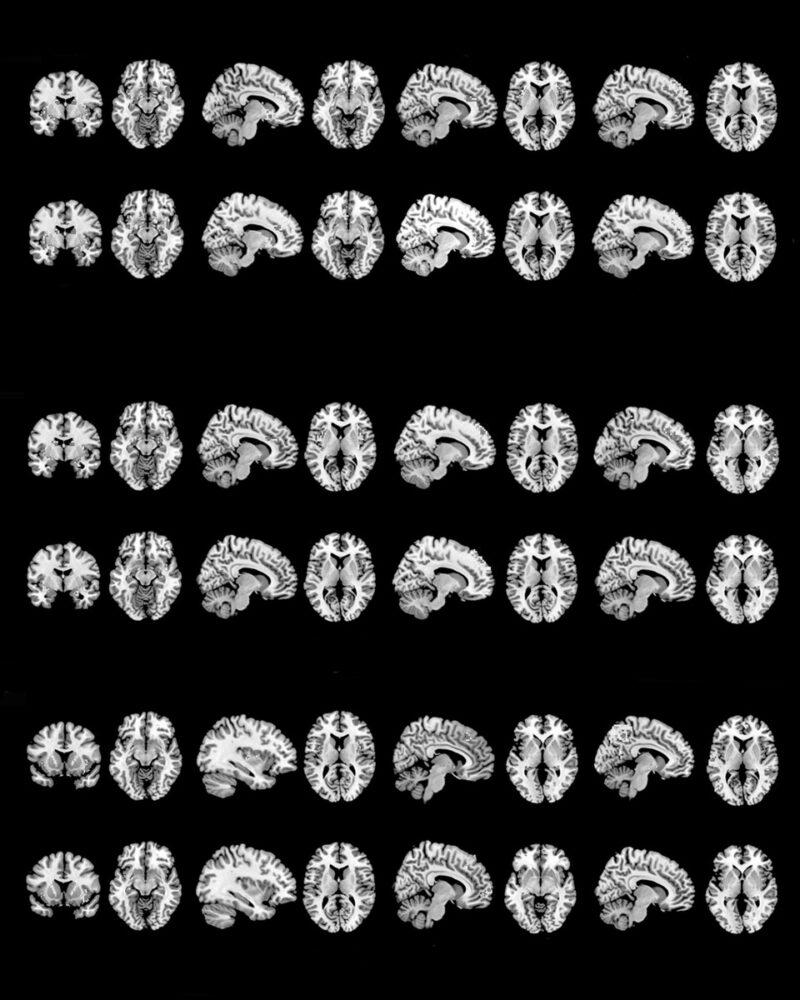

In neurobiology, a love relationship can be divided into two phases: falling in love and a bonding phase. The first is marked by the release of certain biochemical mediators such as dopamine and NGF. In this phase, the areas of the cortex that underlie desire, reward, and sexual excitement are active. Conversely, areas responsible for logic and reasoning are inactivated. The second phase is characterised by “bonding” and the passage to a phase of greater serenity and formation of the couple’s relationship.

This is how the idea of representing our love relationship was born, going to explore, with the method and scientific rigour, the neurobiological processes within our brain, and then repropose them to a possible viewer through some visual metaphors. We, therefore, produced and combined different types of images: from a small sculpture that recalls the molecular composition of dopamine to the neuroimaging of some sections of the brains of people in love, from the NGF sequence inserted into a computer terminal and screenshotted to a plant that alludes to the connection of the synapses of our nervous system.